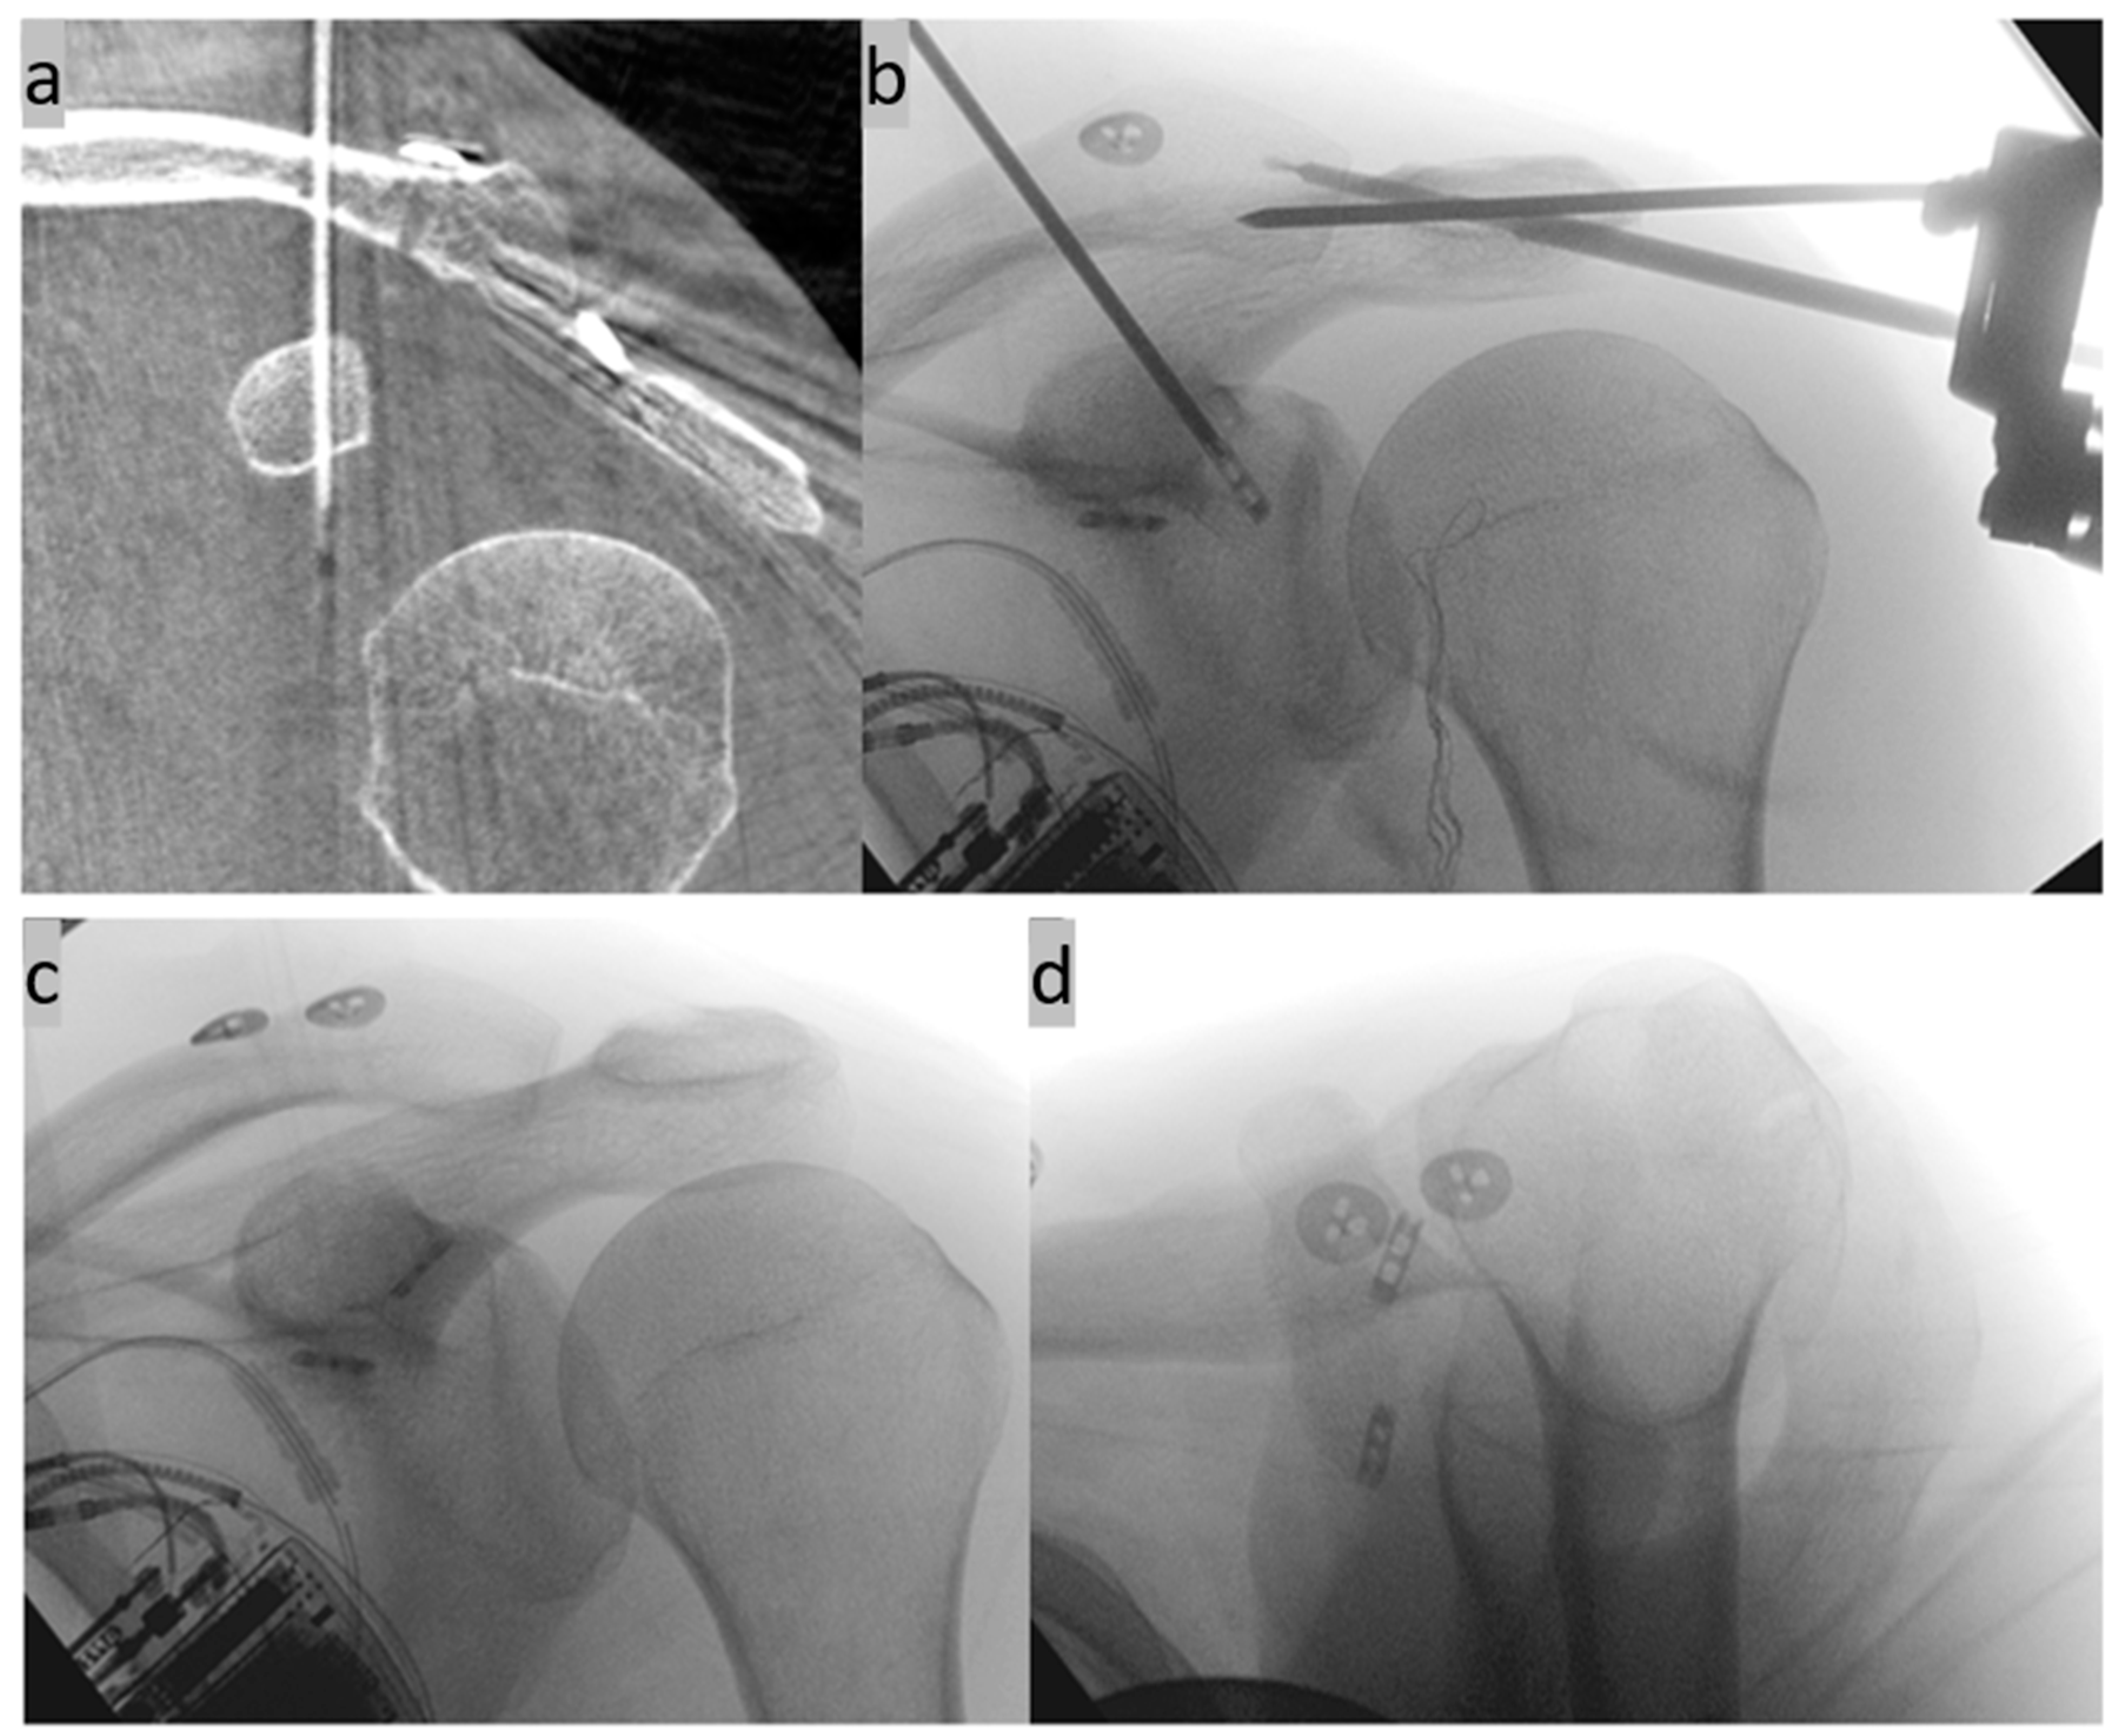

2. Surgical Technique